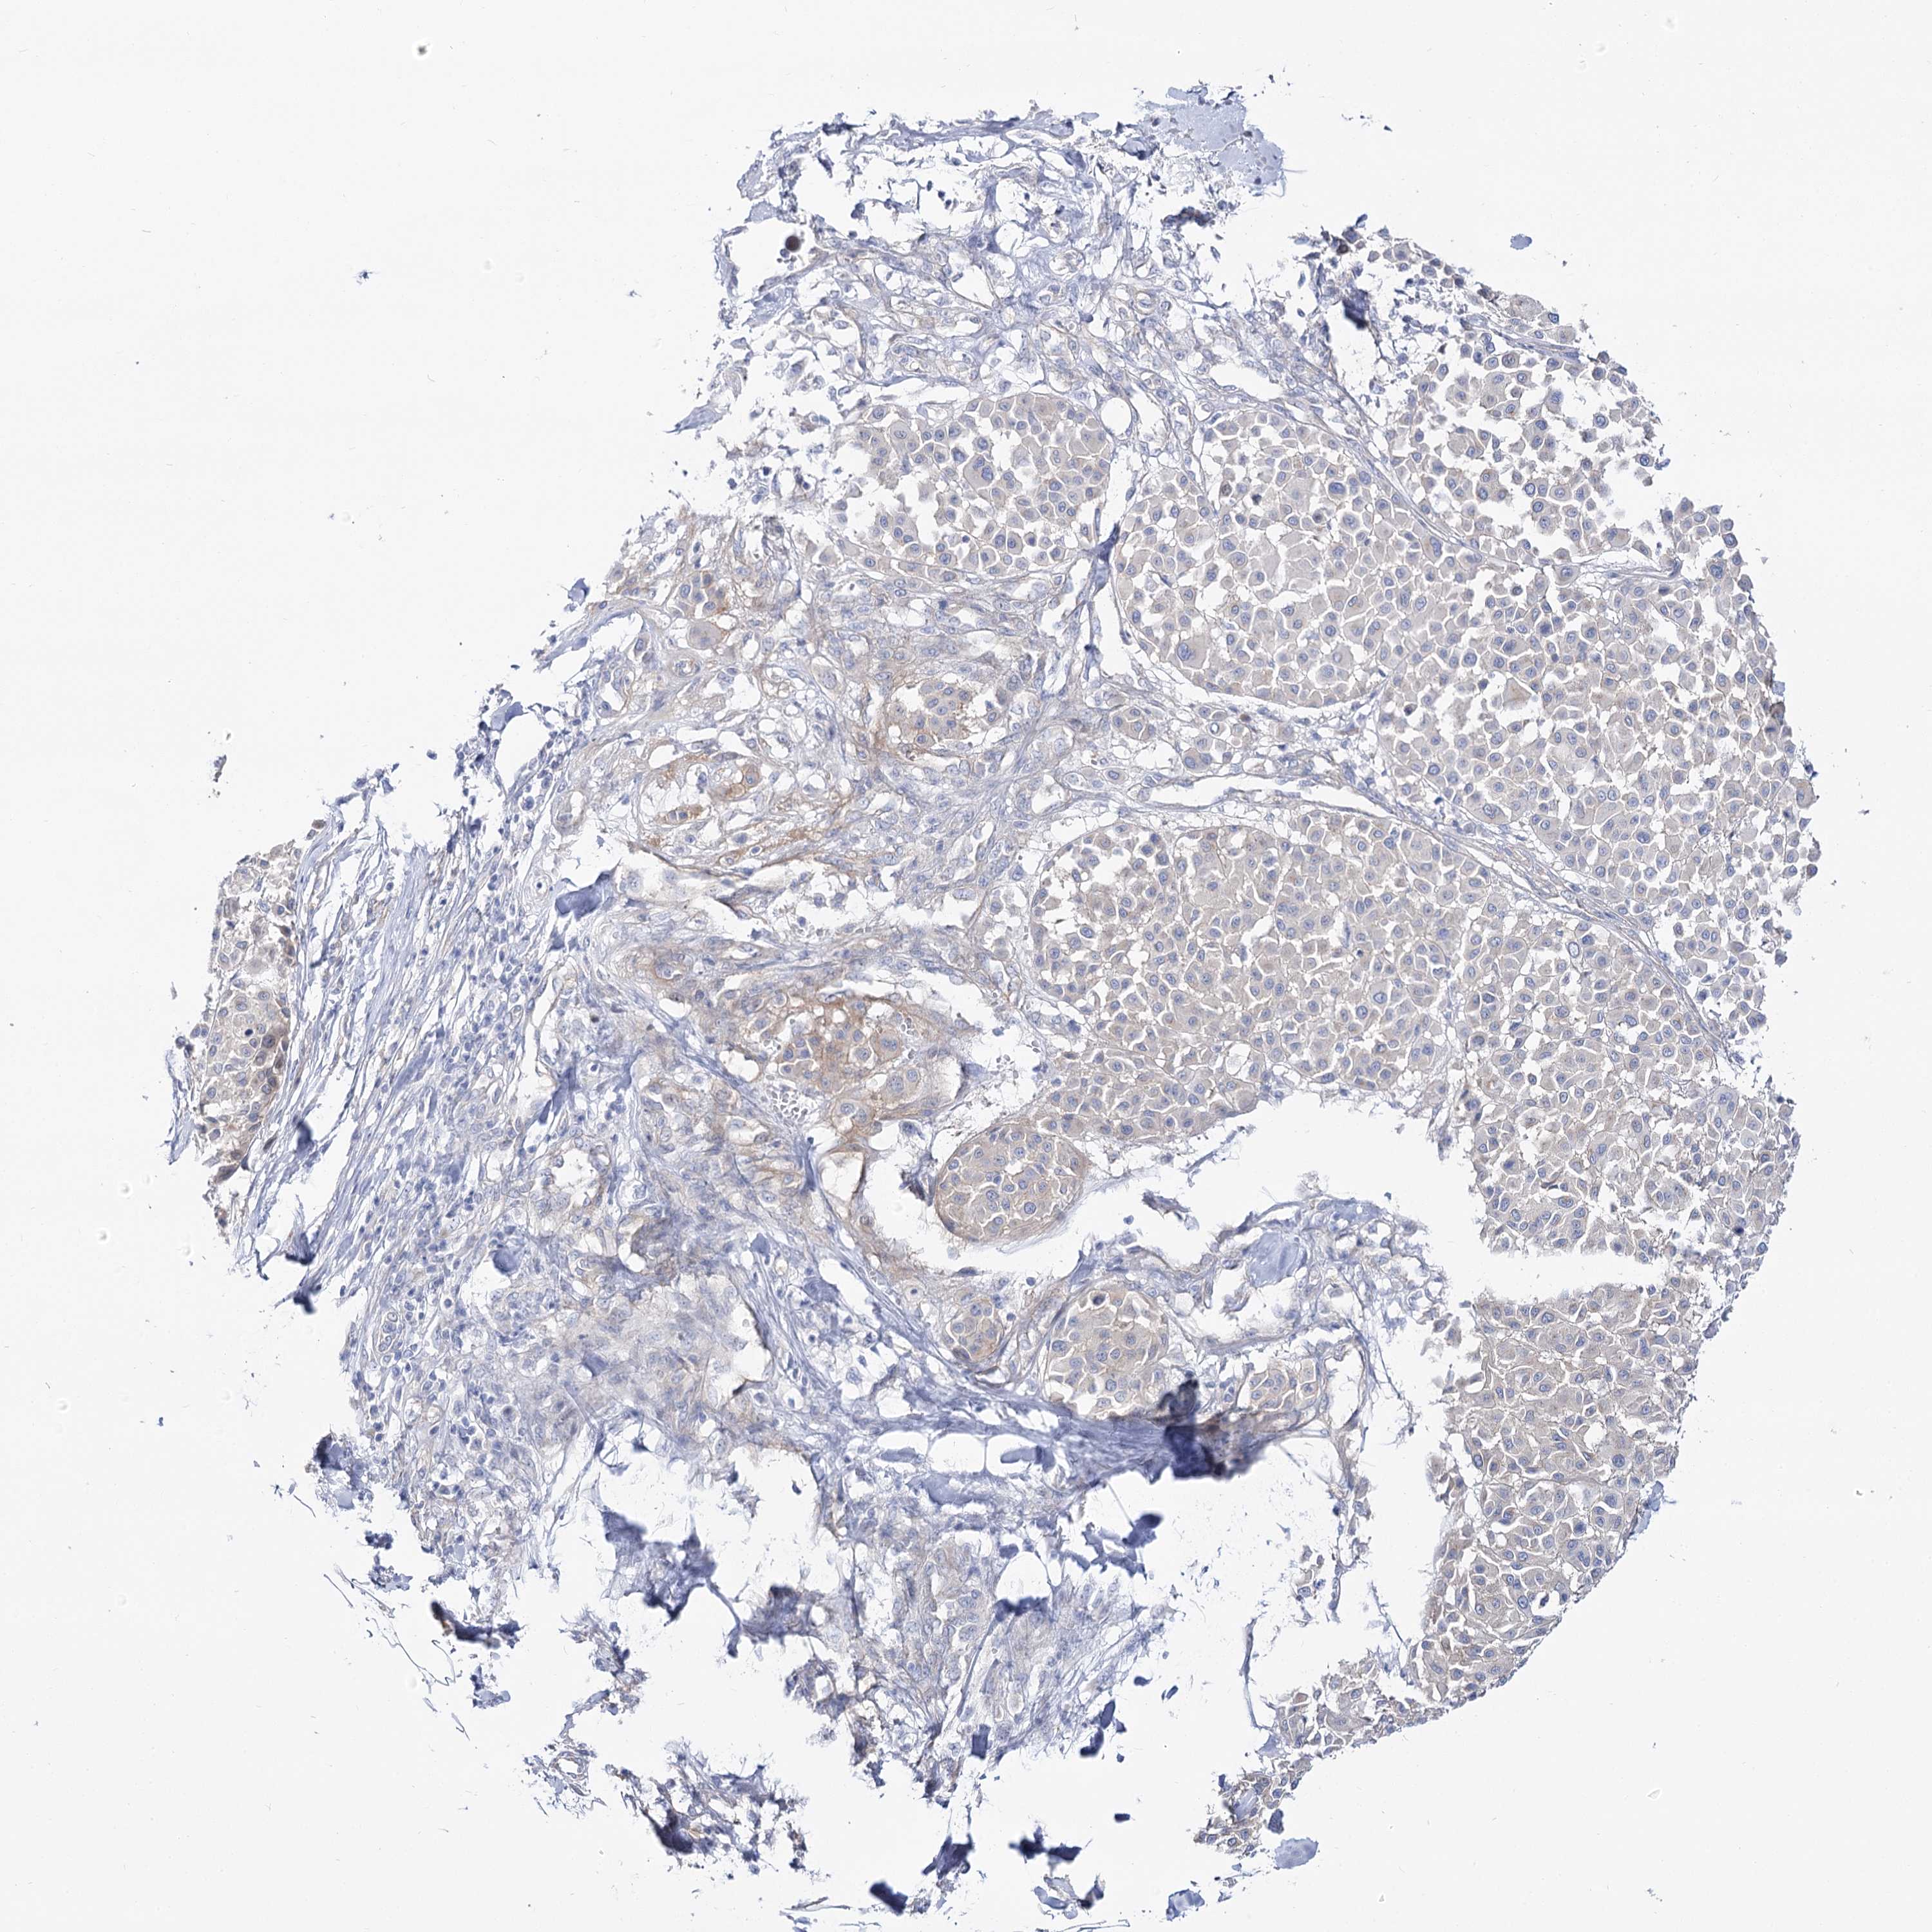

MELANOMA - Protein expressioni

A mouse-over function shows sample information and annotation data. Click on an image to view it in a full screen mode. Samples can be filtered based on level of antibody staining by selecting one or several of the following categories: high, medium, low and not detected. The assay and annotation is described here.

Note that samples used for immunohistochemistry by the Human Protein Atlas do not correspond to samples in the TCGA dataset.

Antibody stainingi

Antibody staining in the annotated cell types in the current human tissue is reported as not detected, low, medium, or high, based on conventional immunohistochemistry profiling in selected tissues. This score is based on the combination of the staining intensity and fraction of stained cells.

Each image is clickable and will lead to virtual microscopy that enables deeper exploration of all samples and also displays staining intensity scores, fraction scores and subcellular localization as well as patient and tissue information for each sample.

Antibody HPA038208

Antibody HPA038209

Staining

High

Medium

Low

Not detected

Intensity

Strong

Moderate

Weak

Negative

Quantity

>75%

75%-25%

<25%

None

Location

Nuclear

Cytoplasmic/membranous

Cytoplasmic/membranous,nuclear

Malignant melanoma, NOS

Malignant melanoma, Metastatic site